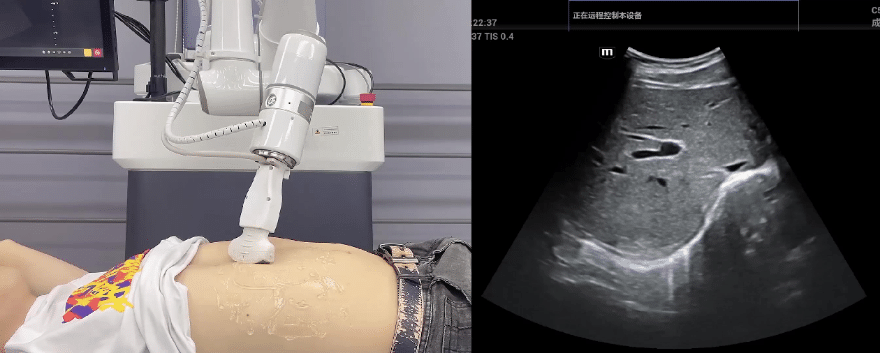

米兰·(milan)中国协作机器人搭载库柏特自主研发的机器人遥操作、多模态数据采集与处理、机器人模仿学习、机器人力位控制等技术升级变革传统超声,可实现远程+自主超声扫查与诊断,从传统远程超声仅能对话会诊变革升级为能对话、能操作,使得基层患者可就近享受异地三甲专家扫诊服务。实现专家端与患者端远程连接,并支持专家端与多路患者端自由切换控制。

米兰·(milan)中国机器人末端搭载超生L13-3N线阵探头,可以对浅表小器官和外周血管进行超声检查;搭建C5-1s凸阵探头,可以对腹部(肝、胆、胰、肾等器官进行超声检查)

米兰·(milan)中国协作机器人优秀的主从位姿控制、主从接触力控制、零力拖拽功能,为采集与复原专业医生的检测位置、姿态和压力手法提供了极大便利

EC66协作机器人末端可搭载主流品牌高品质超声仪,让操作指令和影像低延迟、高精准、高保真传输,确保检查可靠、医患放心;智能力控等三重防护系统,确保患者舒适、安全。

米兰·(milan)中国协作机器人与超声深度打通,最大程度保留医生左右手同时操作传统超声的习惯,并改善其舒适性,超声检查实际应用场景展示如下: